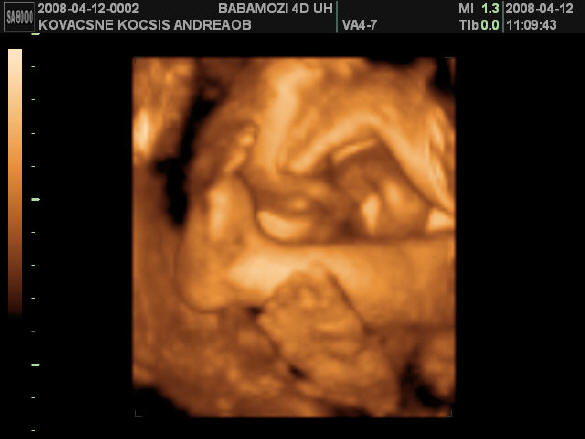

2008.04.12 10:53